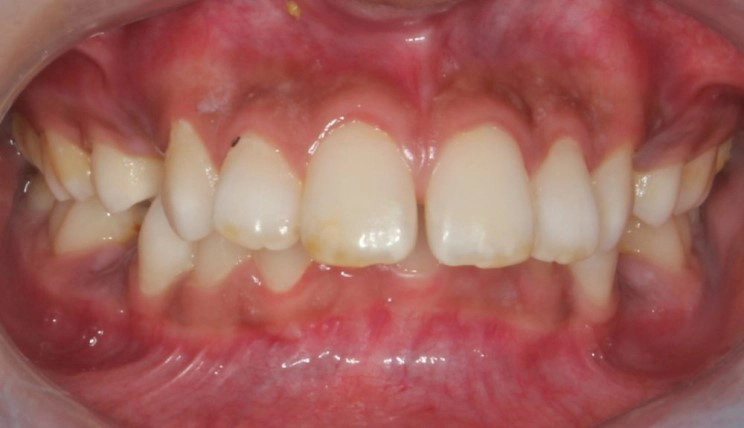

Crowding

Crowding is the condition in which there is a discrepancy between tooth size and space available for the teeth to be aligned in the dental arch

Patient Information:

Age: 17

Gender: female

Invisalign Treatment Option: Invisalign Comprehensive

Total Treatment Time:

29 months